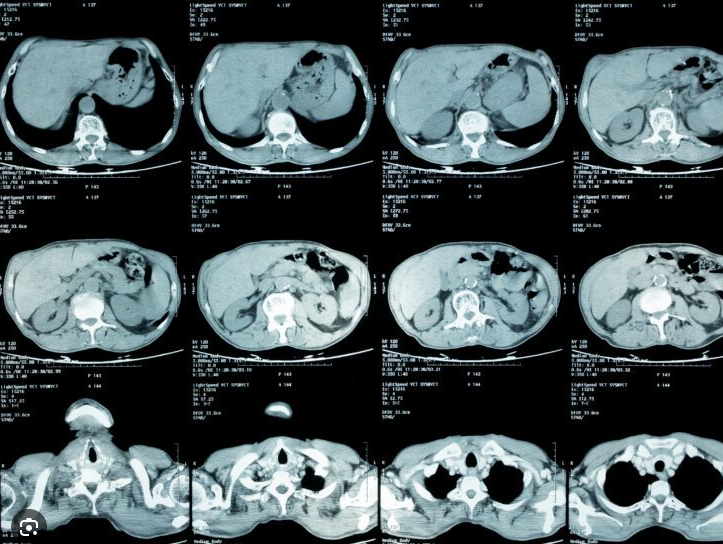

Imaging - First Line Chest radiograph, CT abdomen/pelvis

• CT of abdomen and chest

• MRI for CNS, spleen, lymph nodes, aorta (vasculitis)